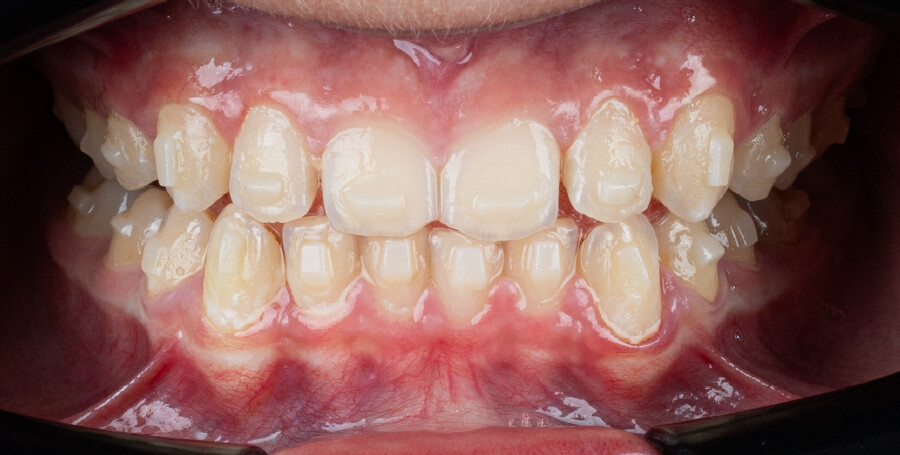

Um paciente do sexo masculino, com 13 anos de idade, apresentou-se com uma mordida profunda, caracterizada pela cobertura quase completa dos incisivos mandibulares. A avaliação clínica revelou apinhamento em ambas as arcadas, rotações dentárias e proclinação dos incisivos laterais superiores, contribuindo para as preocupações estéticas do paciente. O perfil facial era retrusivo, consistente com retrognatismo mandibular, e não foram detectadas anomalias periodontais significativas.

O paciente apresentava uma relação esquelética de Classe II com molares e caninos bilaterais em Classe II e um padrão dentário de Classe II divisão 2. A mordida profunda estava associada a um apinhamento anteroinferior e a uma curva de Spee acentuada. A análise facial revelou boa simetria, um terço facial inferior ligeiramente aumentado e um perfil convexo caracterizado por retrusão mandibular e do mento. A competência labial estava ligeiramente reduzida, com diminuição do ângulo nasolabial e leve tensão do músculo mentoniano, fatores que comprometiam a harmonia facial global.